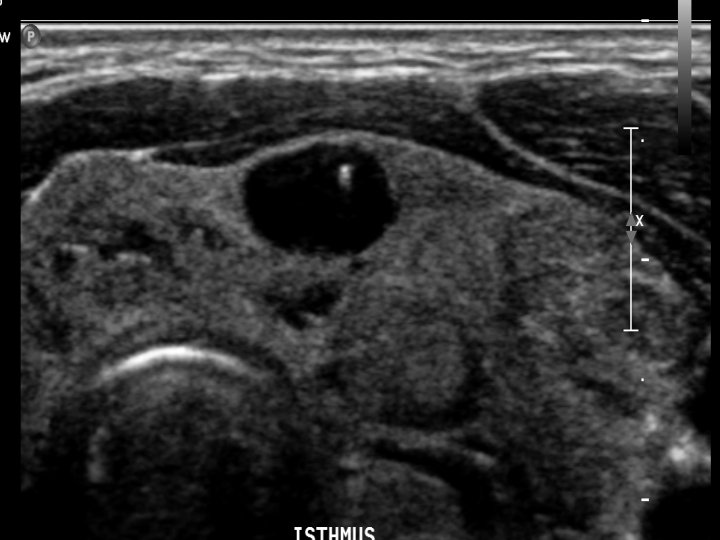

Cysts n n n True cysts are uncommon Cystic appearing lesions are usually degenerating adenomas or colloid nodules Sonographic appearance: n n n display cystic characteristics may have internal echoes and irregular walls Alcohol ablation is a treatment option

Cysts